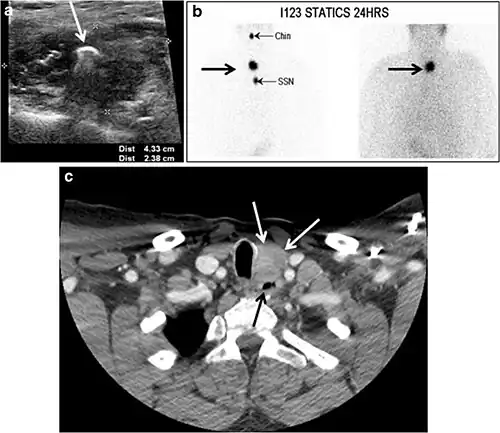

Fig. 7. A 51-year-old female patient post total thyroidectomy for PTC with elevated thyroglobulin measurement. an Axial non-enhanced CT scan of the neck at the level of the thyroid bed demonstrates a well-defined, rounded, homogenously dense soft tissue situated between the trachea and left internal jugular vein (white arrow). b Transverse ultrasound image of the neck demonstrates a well-defined, homogeneous, hypoechoic soft tissue nodule measuring 6 mm (white arrow) with no detected micro-calcifications. Biopsy showed a predominantly residual normal thyroid tissue with micro-foci of PTC.[1] -